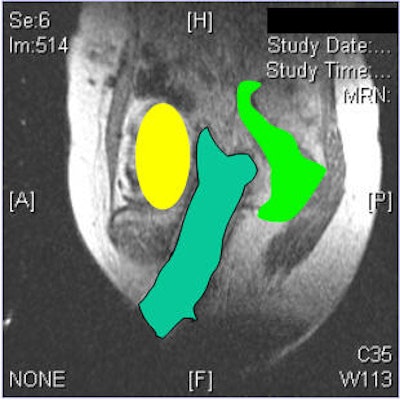

| No inadvertent insertion of interstitial catheter into bladder or rectum noted on CT (below) after MR (above). |

Scanning was done on a 0.5-tesla MR therapy unit. T1-weighted and T2-weighted images were acquired. The patients had epidurals and were under general anesthesia. The foley balloon was inserted followed by the obturator and the template, which was sutured in four corners. A median number of 12.9 interstitial catheters were placed.

"We then have the radiologist look at the series of MR images obtained and reposition the obturator so that the needles were directed at the tumor," Viswanathan explained. "We then do the insertion on real-time MR guidance. It doesn't mean that as we are putting in the needles, we are seeing them go in. It does mean that we put the needles in, scan the patient in ... axial or sagittal planes, look at where the needle is, and readjust. Then we get final MR imaging after all the needles have been inserted and we're happy with our tumor volume."

The results showed that protection of the bladder and rectum was achieved. In all 10 cases, there was no inadvertent insertion.